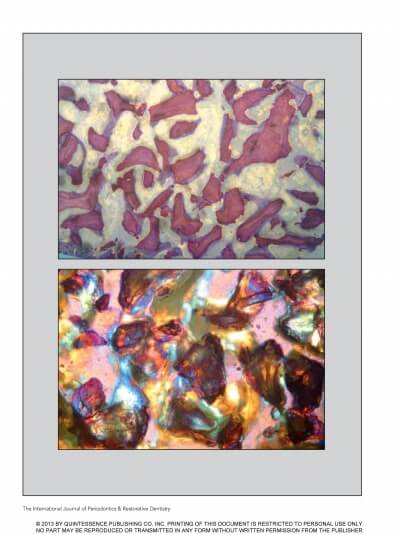

SINUS FLOOR AUGMENTATION WITH HYDROPNEUMATIC TECHNIQUE

SINUS AUGMENTATION PROCEDURES